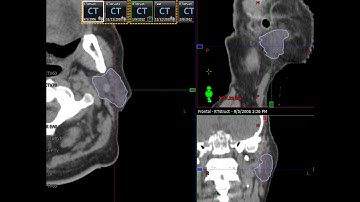

Varian Eclipse Contouring Basics